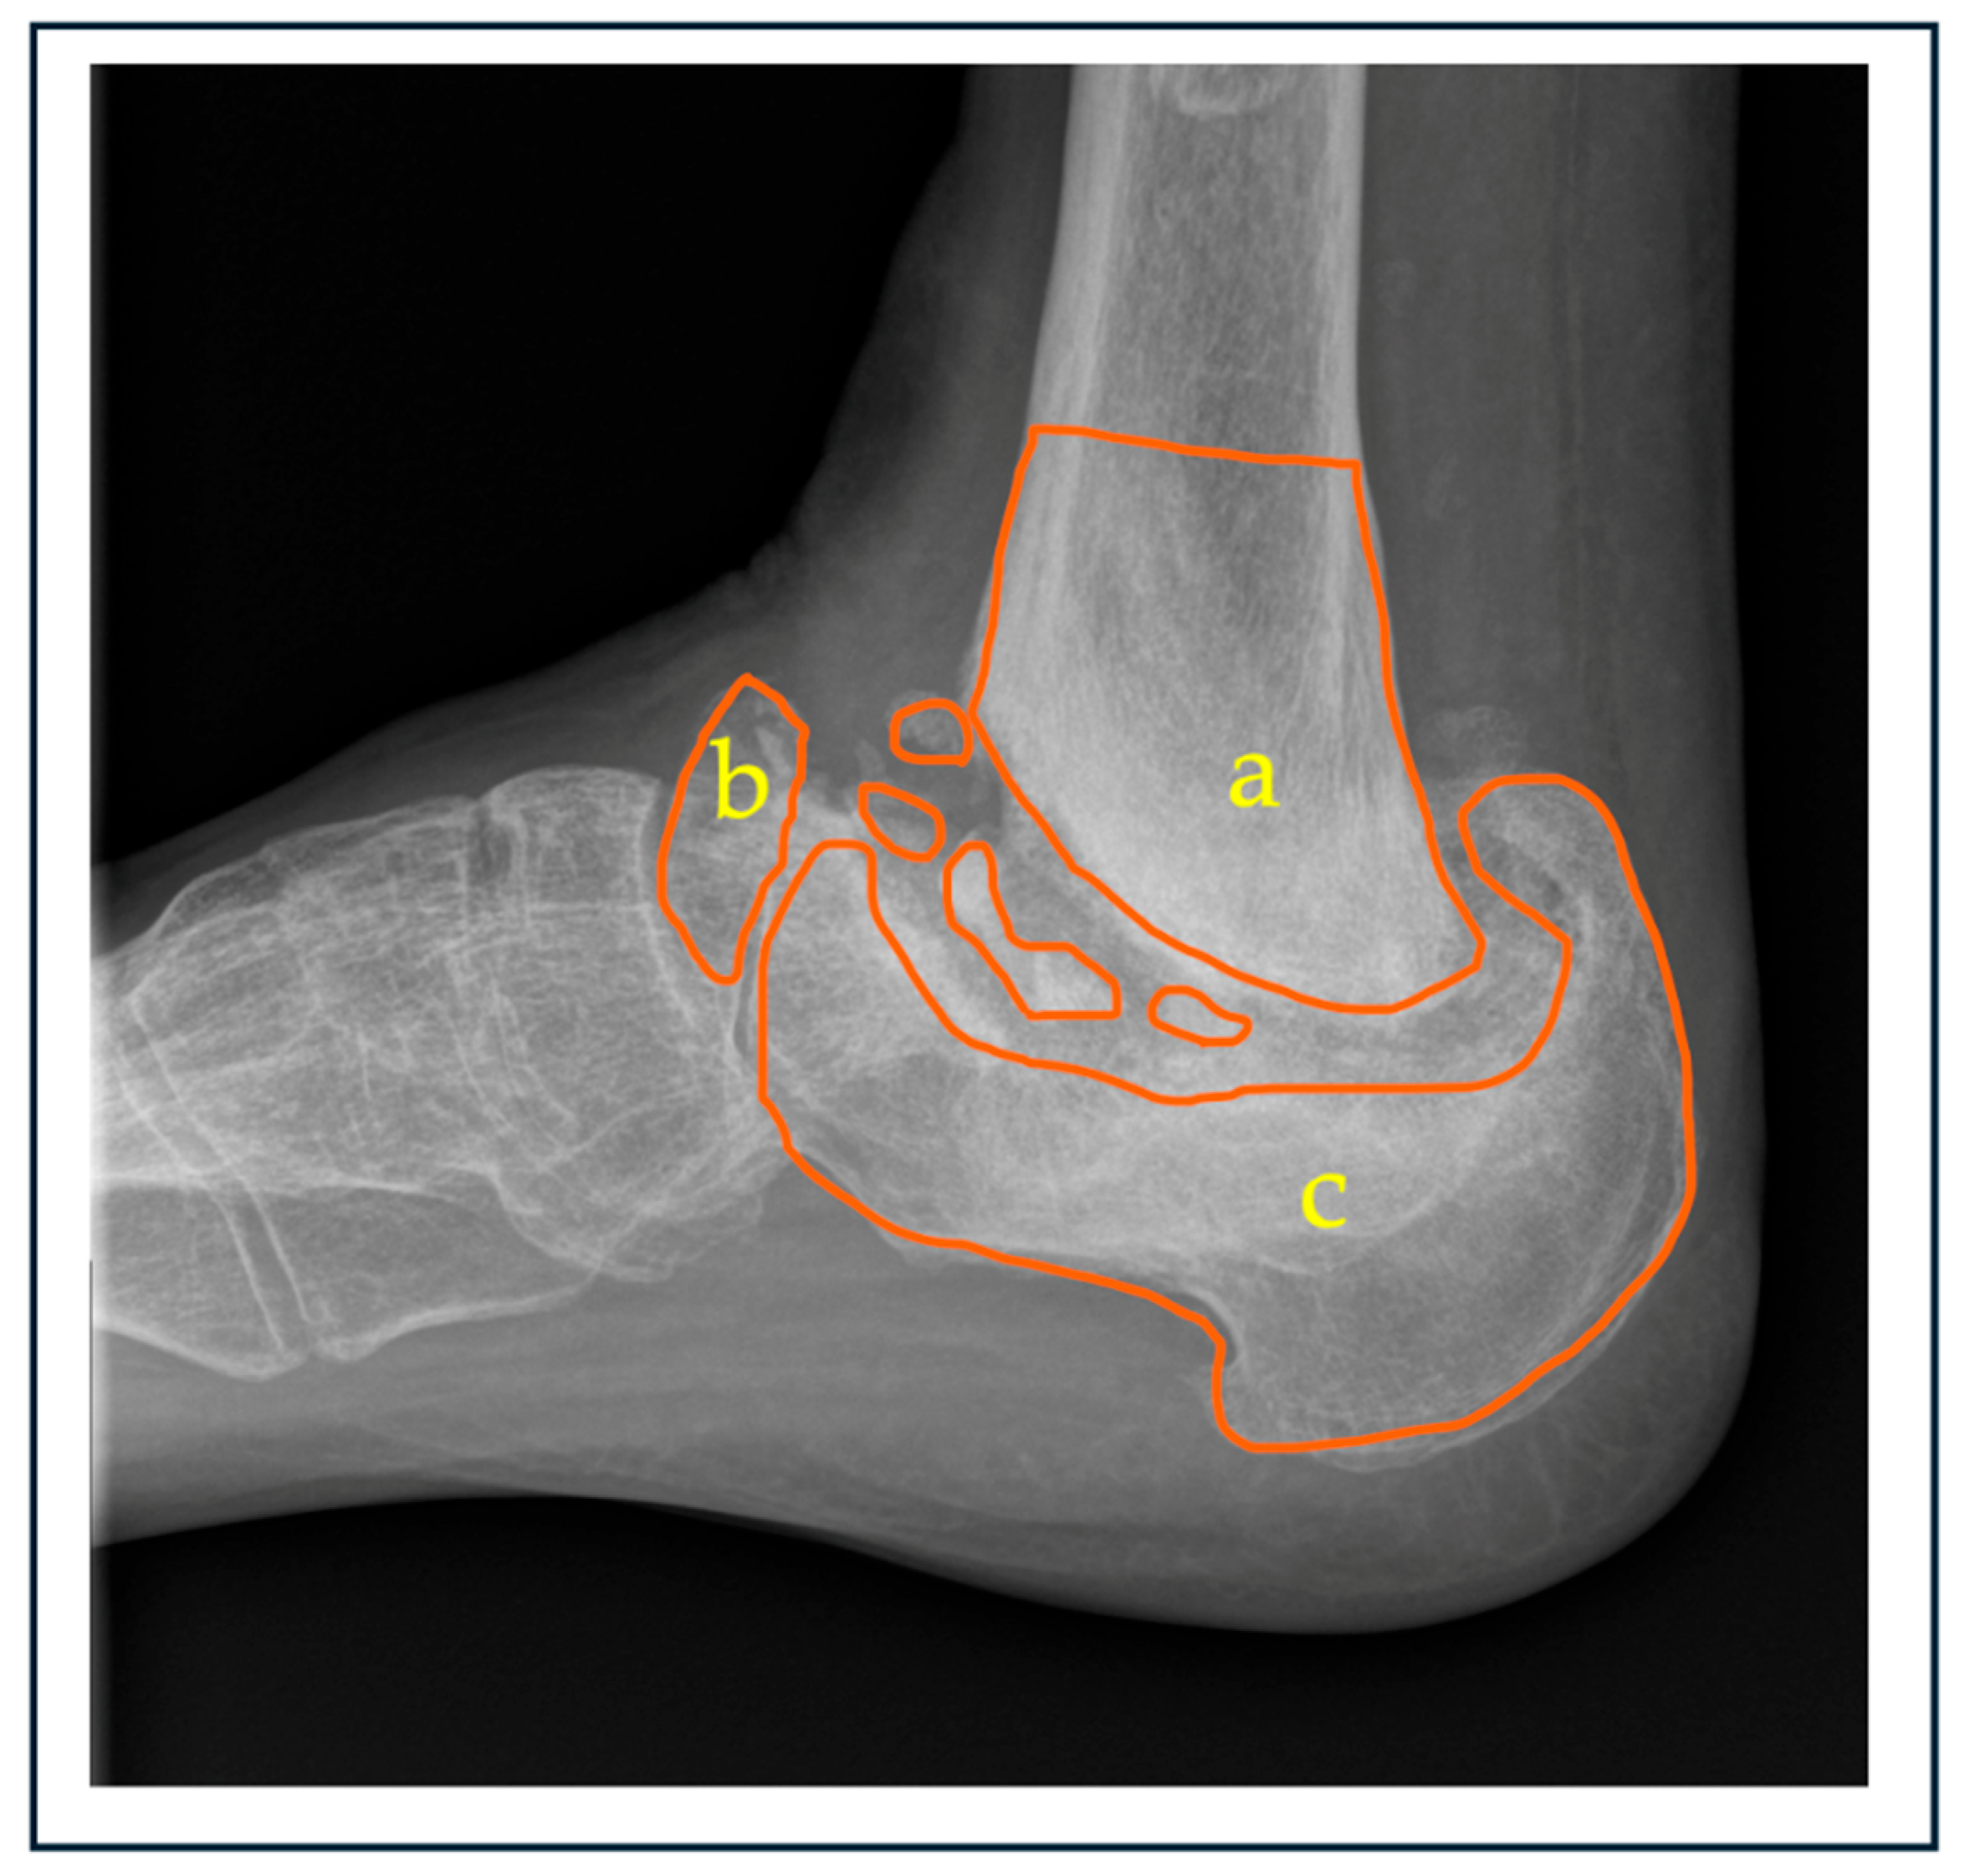

Next, from the proposed classification, “B” represents bone stock, which denotes the presence of bone loss, with subtypes a, b, c and d. These subtypes refer to the tibia, talus, calcaneum, and combined form of bone loss, respectively. All patients in this review were classified based on plain weight-bearing ankle X-rays. Figure 2 shows the sagittal view of an ankle, with osteodestruction involving the distal tibia and calcaneum, with a severely fragmented talus.

Figure 2. Radiograph representing anatomical sites of possible bone loss in ankle Charcot: a. distal tibia, b. talus, and c. calcaneum. The extent of osseous loss can vary depending on the chronicity of the condition.